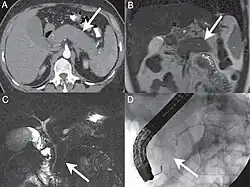

A. Axial CT image in the pancreatic parenchymal phase shows the typical enlarged, poorly enhancing gland. B. Coronal T2 Weighted MR image demonstrates low signal intensity in the pancreas due to the diffuse fibrosis in the gland. C. Coronal MRCP image depicts a diffusely irregular pancreatic duct with stenosis distally in the pancreatic head. D. ERCP confirms the MR findings including the ductal stenosis.

Computed tomography (CT) findings in AIP include a diffusely enlarged hypodense pancreas or a focal mass that may be mistaken for a pancreatic malignancy.[8] A low-density, capsule-like rim on CT (possibly corresponding to an inflammatory process involving peripancreatic tissues) is thought to be an additional characteristic feature (thus the mnemonic: sausage-shaped). Magnetic resonance imaging (MRI) reveals a diffusely decreased signal intensity and delayed enhancement on dynamic scanning. The characteristic ERCP finding is segmental or diffuse irregular narrowing of the main pancreatic duct, usually accompanied by an extrinsic-appearing stricture of the distal bile duct. Changes in the extrapancreatic bile duct similar to those of primary sclerosing cholangitis (PSC) have been reported.